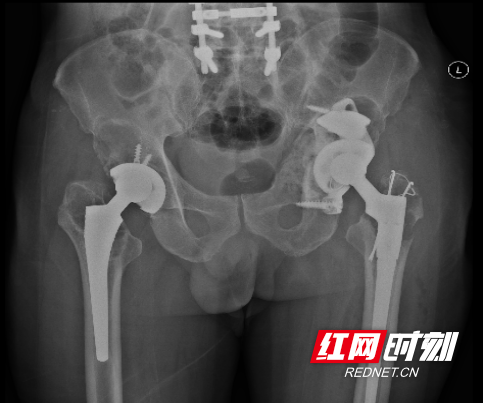

术后患者复查X线,假体位置满意

经过精心的术前准备,陈志伟带领团队医师联合该院麻醉科和手术室,成功地为该患者施行了全髋关节置换术后严重骨吸收复杂翻修手术。术中精细配合,专业团队保驾护航,自体血回收,大大减少出血风险,整个手术过程顺利,患者术后感觉极好,基本无痛,可轻松完成踝泵运动。术后患者复查X线,假体位置满意。